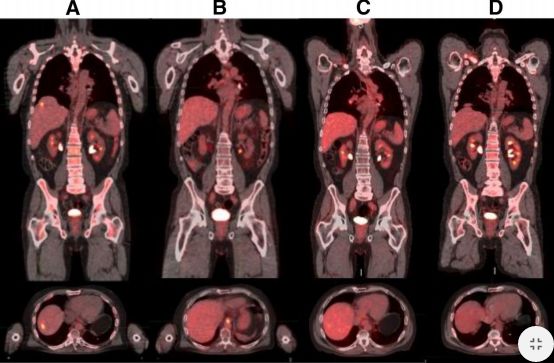

(一)患者检测到MET扩增(12个拷贝数),使用克唑 替尼后,肝转移消失,疾病控制达到5个月。

(二)胃癌患者检测到FGFR2扩增,患者对FGFR2抑制剂AZD4547有效,治疗6个月后,肝转移灶基本消失。